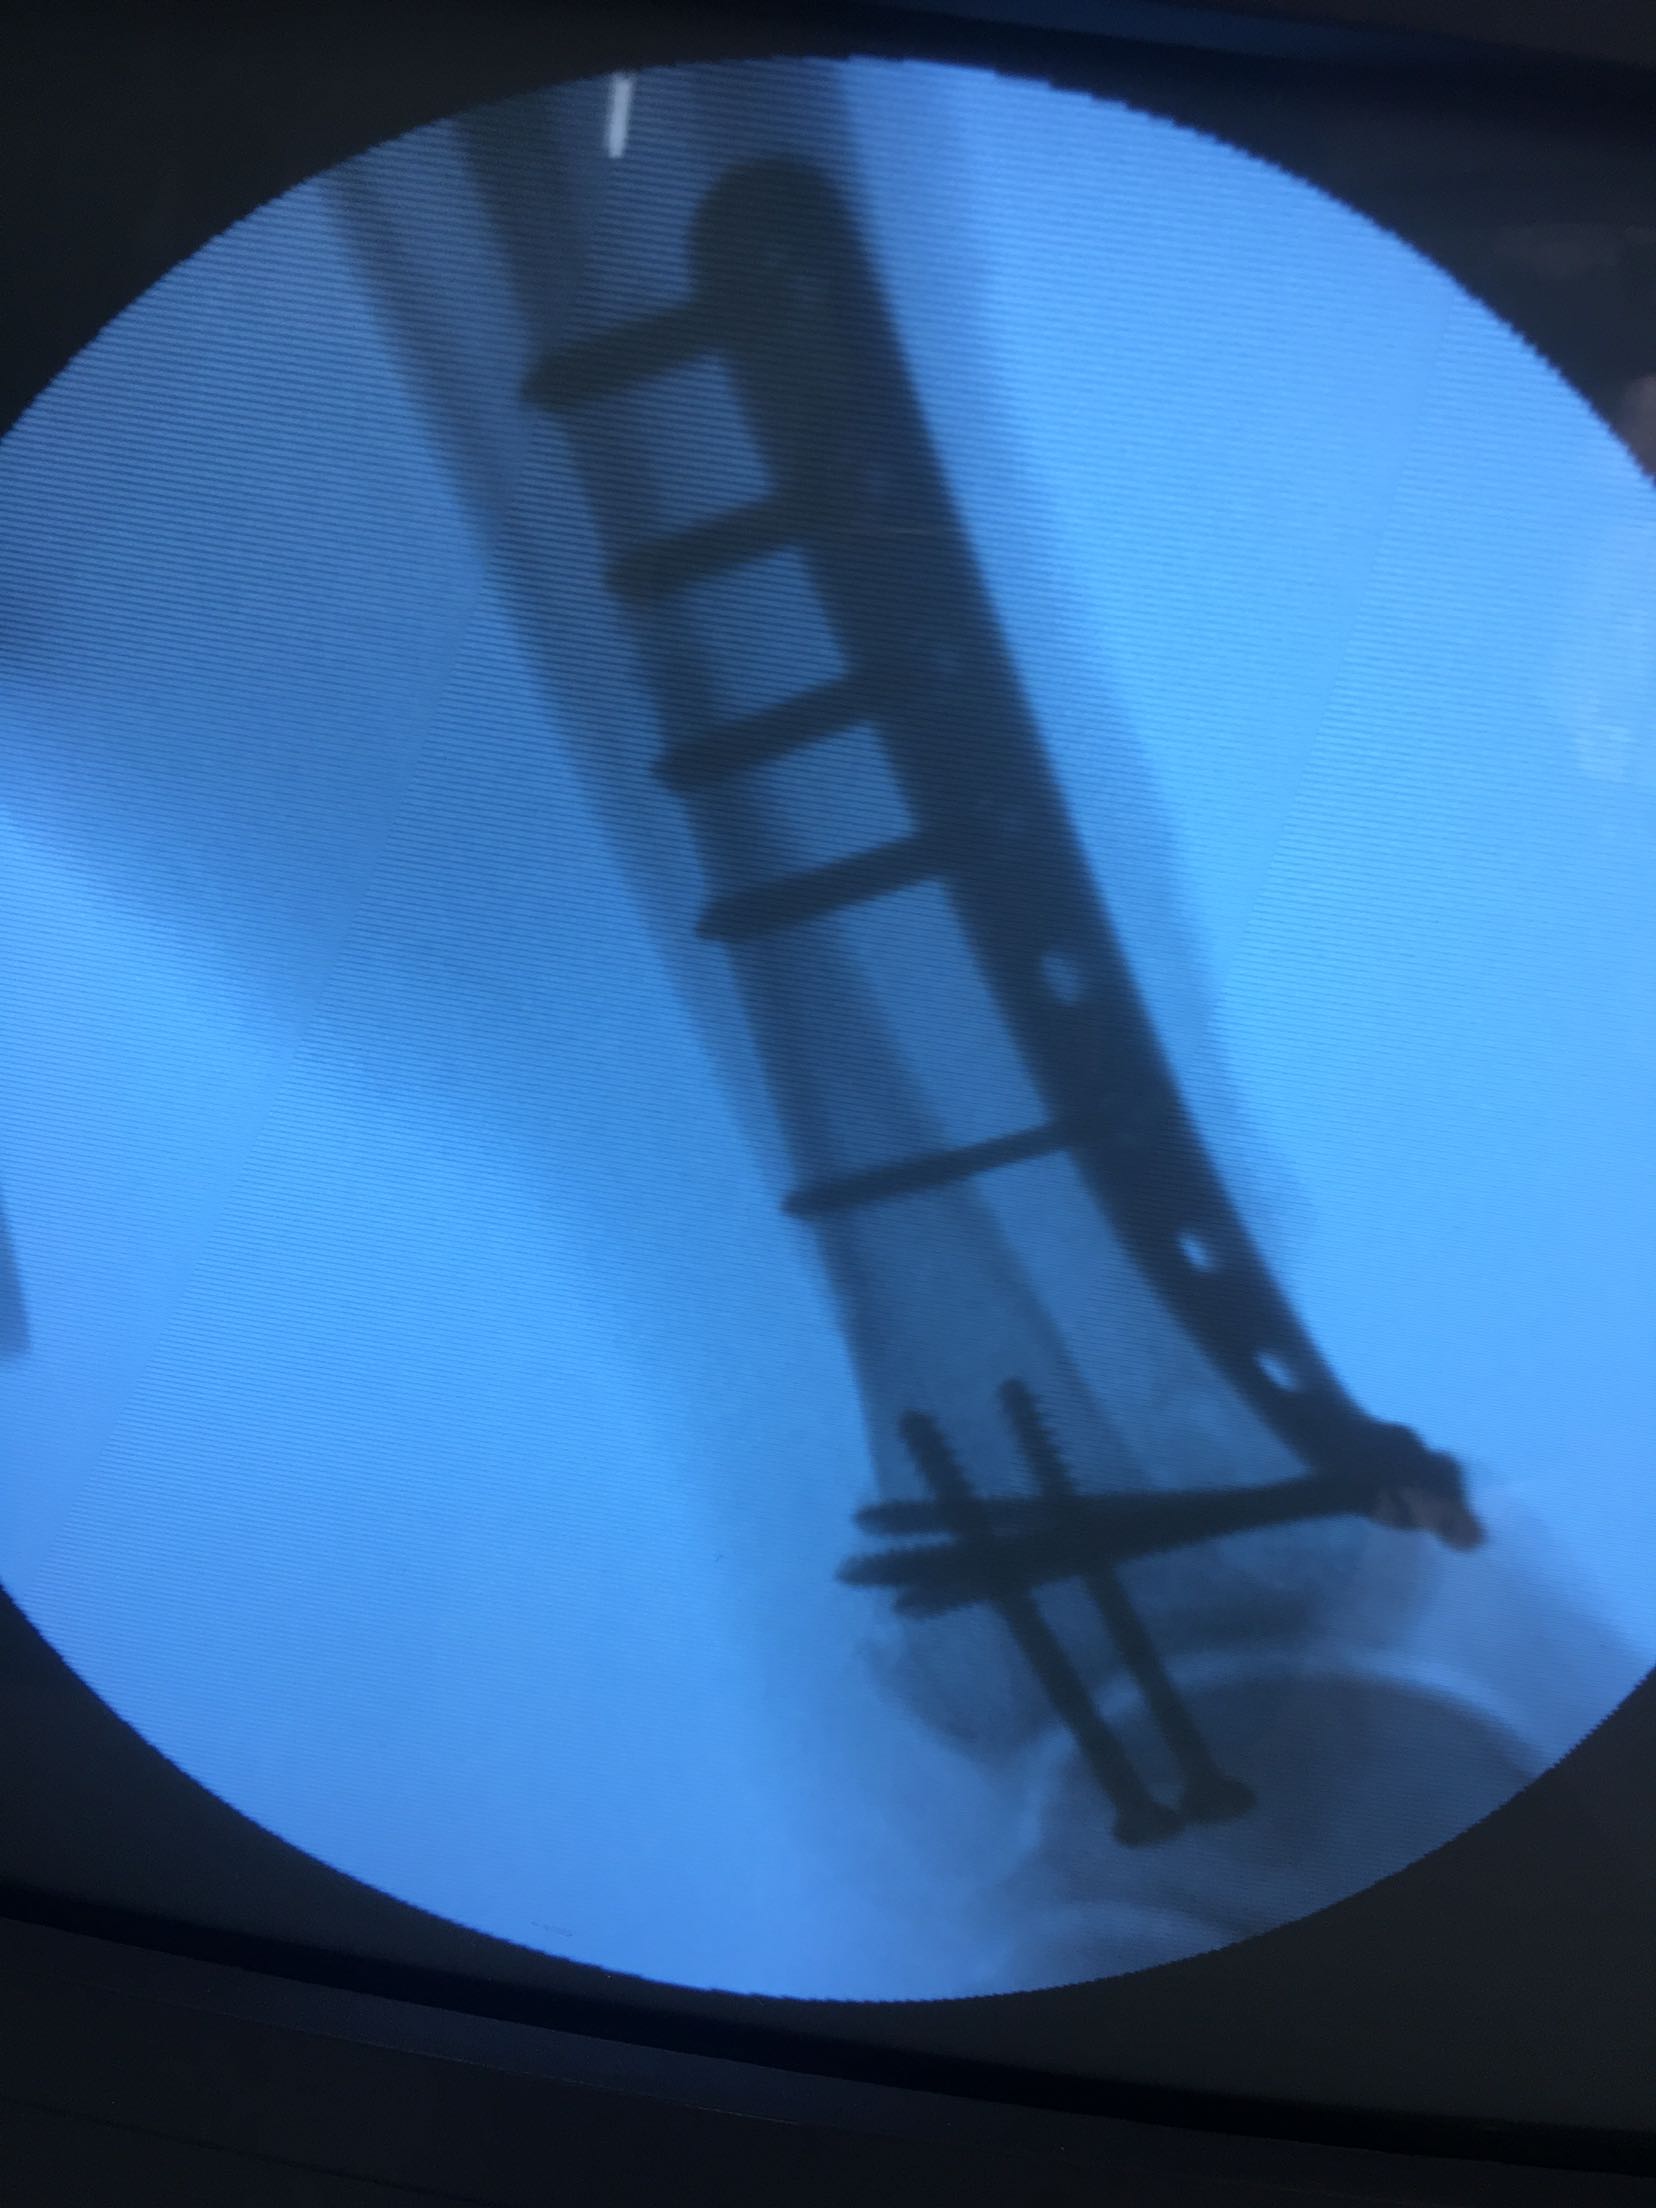

完善检查,在腰麻下行切复内固定术,术后制动,消肿抗炎处理。